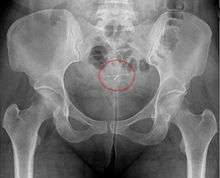

- A "lost coil" occurs when the thread cannot be felt by a woman on routine checking and is not seen on speculum examination.[42] Various thread collector devices or simple forceps may then be used to try to grasp the device through the cervix.[43] In the rare cases when this is unsuccessful, an ultrasound scan may be arranged to check the position of the coil and exclude its perforation through into the abdominal cavity or its unrecognised previous expulsion.